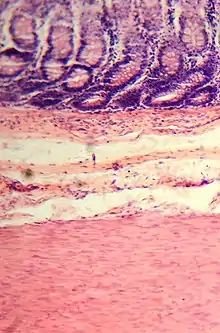

Histología del intestino grueso

Presenta criptas de Lieberkühn, no tiene vellosidades ni pliegues circulares.[44] Presenta, en la túnica serosa, evaginaciones. Una evaginación llena de tejido adiposo constituye un apéndice omental.

En el intestino grueso hay una gran cantidad de exocrinocitos caliciformes. Las poblaciones celulares epiteliales son las mismas del intestino delgado.[45][46]

La diferencia más obvia con el intestino delgado es que es más ancho y que presenta una capa muscular longitudinal que se reduce a tres estructuras en forma de correa, de unos 5 milímetros de anchura, conocidas como taeniae coli, que empiezan en la base del apéndice y se extienden desde el ciego hasta el recto.[2] La capa mucosa de su pared está formada por epitelio columnar simple y, en vez de tener las vellosidades del intestino delgado, el intestino grueso presenta criptas intestinales.[3] A pesar de que los dos intestinos tienen células en forma de cáliz, al intestino grueso son más numerosas. La serosa externa es otra capa de tejido conectivo muy delgada que se continúa focalmente con el peritoneo.